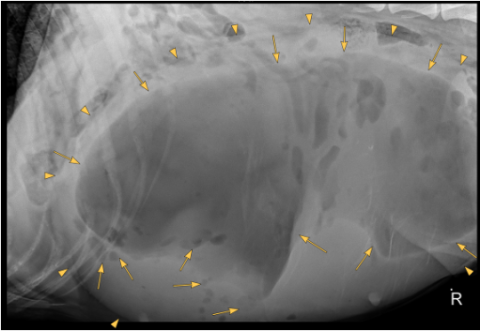

There is severe distention of the abdomen. As far as included the extra-abdominal soft tissues are within normal limits. There are 8 lumbar vertebrae, otherwise the bony structures are within normal limits.

A large well-defined, rounded soft tissue mass is noted in the caudal mid and cranial abdomen. The mass is filled with combination of fluid ( yellow arrow points) and gas (yellow arrows) and originating from the uterus.

The mass is displacing the gastrointestinal tract dorsally, cranially and laterally.

Large fluid and gas-filled mass in the caudal, mid and cranial abdomen originating from the uterus (emphysematous pyometra). Considering the shape of the mass a torsion is suspected.